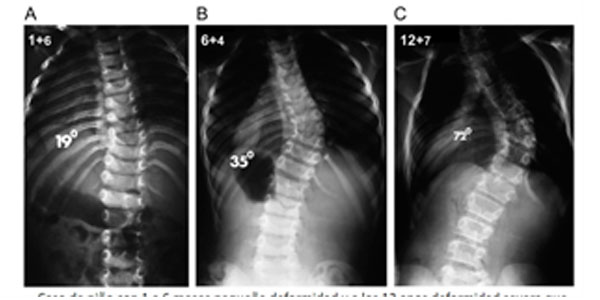

Paciente de 1 año y 8 meses con escoliosis congénita progresiva, se realizó resección de hemivertebra con colocación de tornillos transpediculares